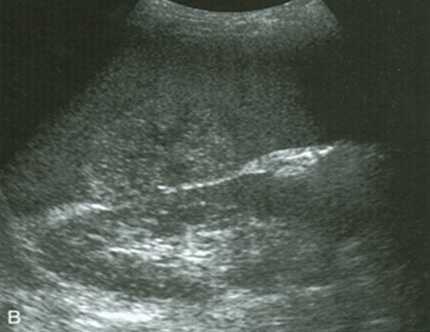

Разрывы селезенки достоверно демонстрируются на ультразвуковом исследовании при условии, что селезенка может быть адекватно визуализирована. Ее часто бывает трудно лоцировать после травмы, так как пациент обычно очень чувствителен к области интереса. Разрыв виден как анэхогенный или гипоэхогенный дефект края селезенки и паренхимы. Это происходит из-за скопления крови в разрыве. По мере сгущения крови разрыв на УЗИ становится эхогенным. Обширные рваные раны могут пересекать оба капсульных края, что приводит к полному перелому селезенки.

- Видимые рваные раны.

- Перелом селезенки (разрыв по всей ширине селезенки).

- Гетерогенная паренхима (ушиб или гематома).

- Периспленальная жидкость.

Ультразвуковая картина, как и при любой острой гематоме, по внешнему виду от свежей крови может быть гиперэхогенной и ее бывает трудно отличить от обычной селезенки. Когда гематома начинает разжижаться, то в центре она становится гипоэхогенной и ее легче обнаружить. Наконец, после того, как она организовалась, то может выглядеть как линейные гиперэхогенные включения или при лизисе стать кистозной. Субкапсулярная жидкость видно только под капсулой селезенки, которая обычно видна в форме полумесяца. Если произошел разрыв селезенки тогда жидкость может быть видна во фланке или в остальной части брюшной полости.